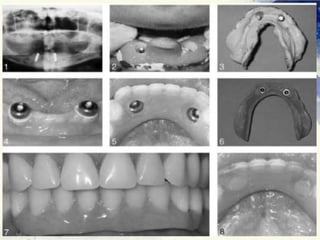

Implant overdenture

Clinical Procedures

Treatment Planning

Patient Selection

◦ Medical History.

◦ Oral Hygiene.

◦ Compliance.

◦ Motivation.

Abutment selection.

◦ Position.

◦ Number of abutments

◦ Periodontal evaluation.

◦ Endodontic evaluation.

◦ Decay or previous restorations.

Inter-arch space.